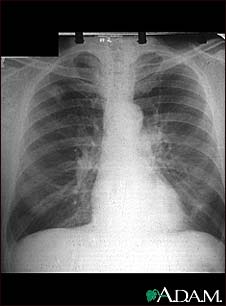

Adenocarcinoma - chest X-ray

This chest x-ray shows adenocarcinoma of the lung. There is a rounded light spot in the right upper lung (left side of the picture) at the level of the second rib. The light spot has irregular and poorly defined borders and is not uniform in density. Diseases that may cause this type of x-ray result would be tuberculous or fungal granuloma, and malignant or benign tumors.